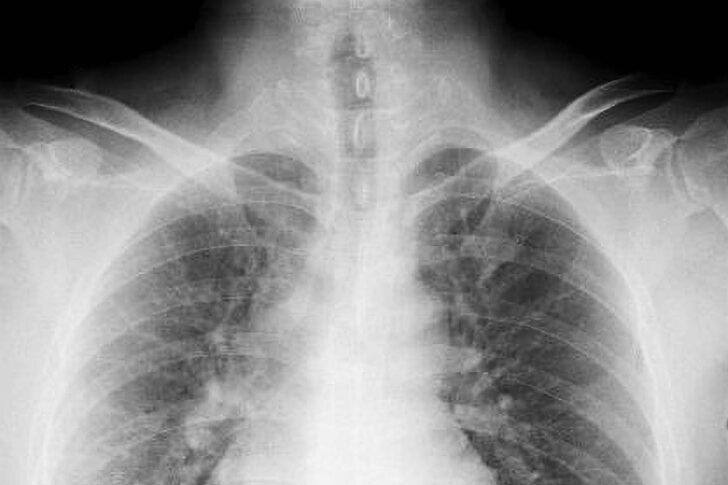

肺がんは、何らかの原因により肺胞や気管支の細胞ががん化することで発生します。

がん細胞は周囲の組織を壊しながら増殖を繰り返し、進行すると血管やリンパ管を介してほかの臓器や組織に転移していきます。肺がんの転移しやすい部位には、同側又は反対側の肺・リンパ節・肝臓・脳・骨などが挙げられます。